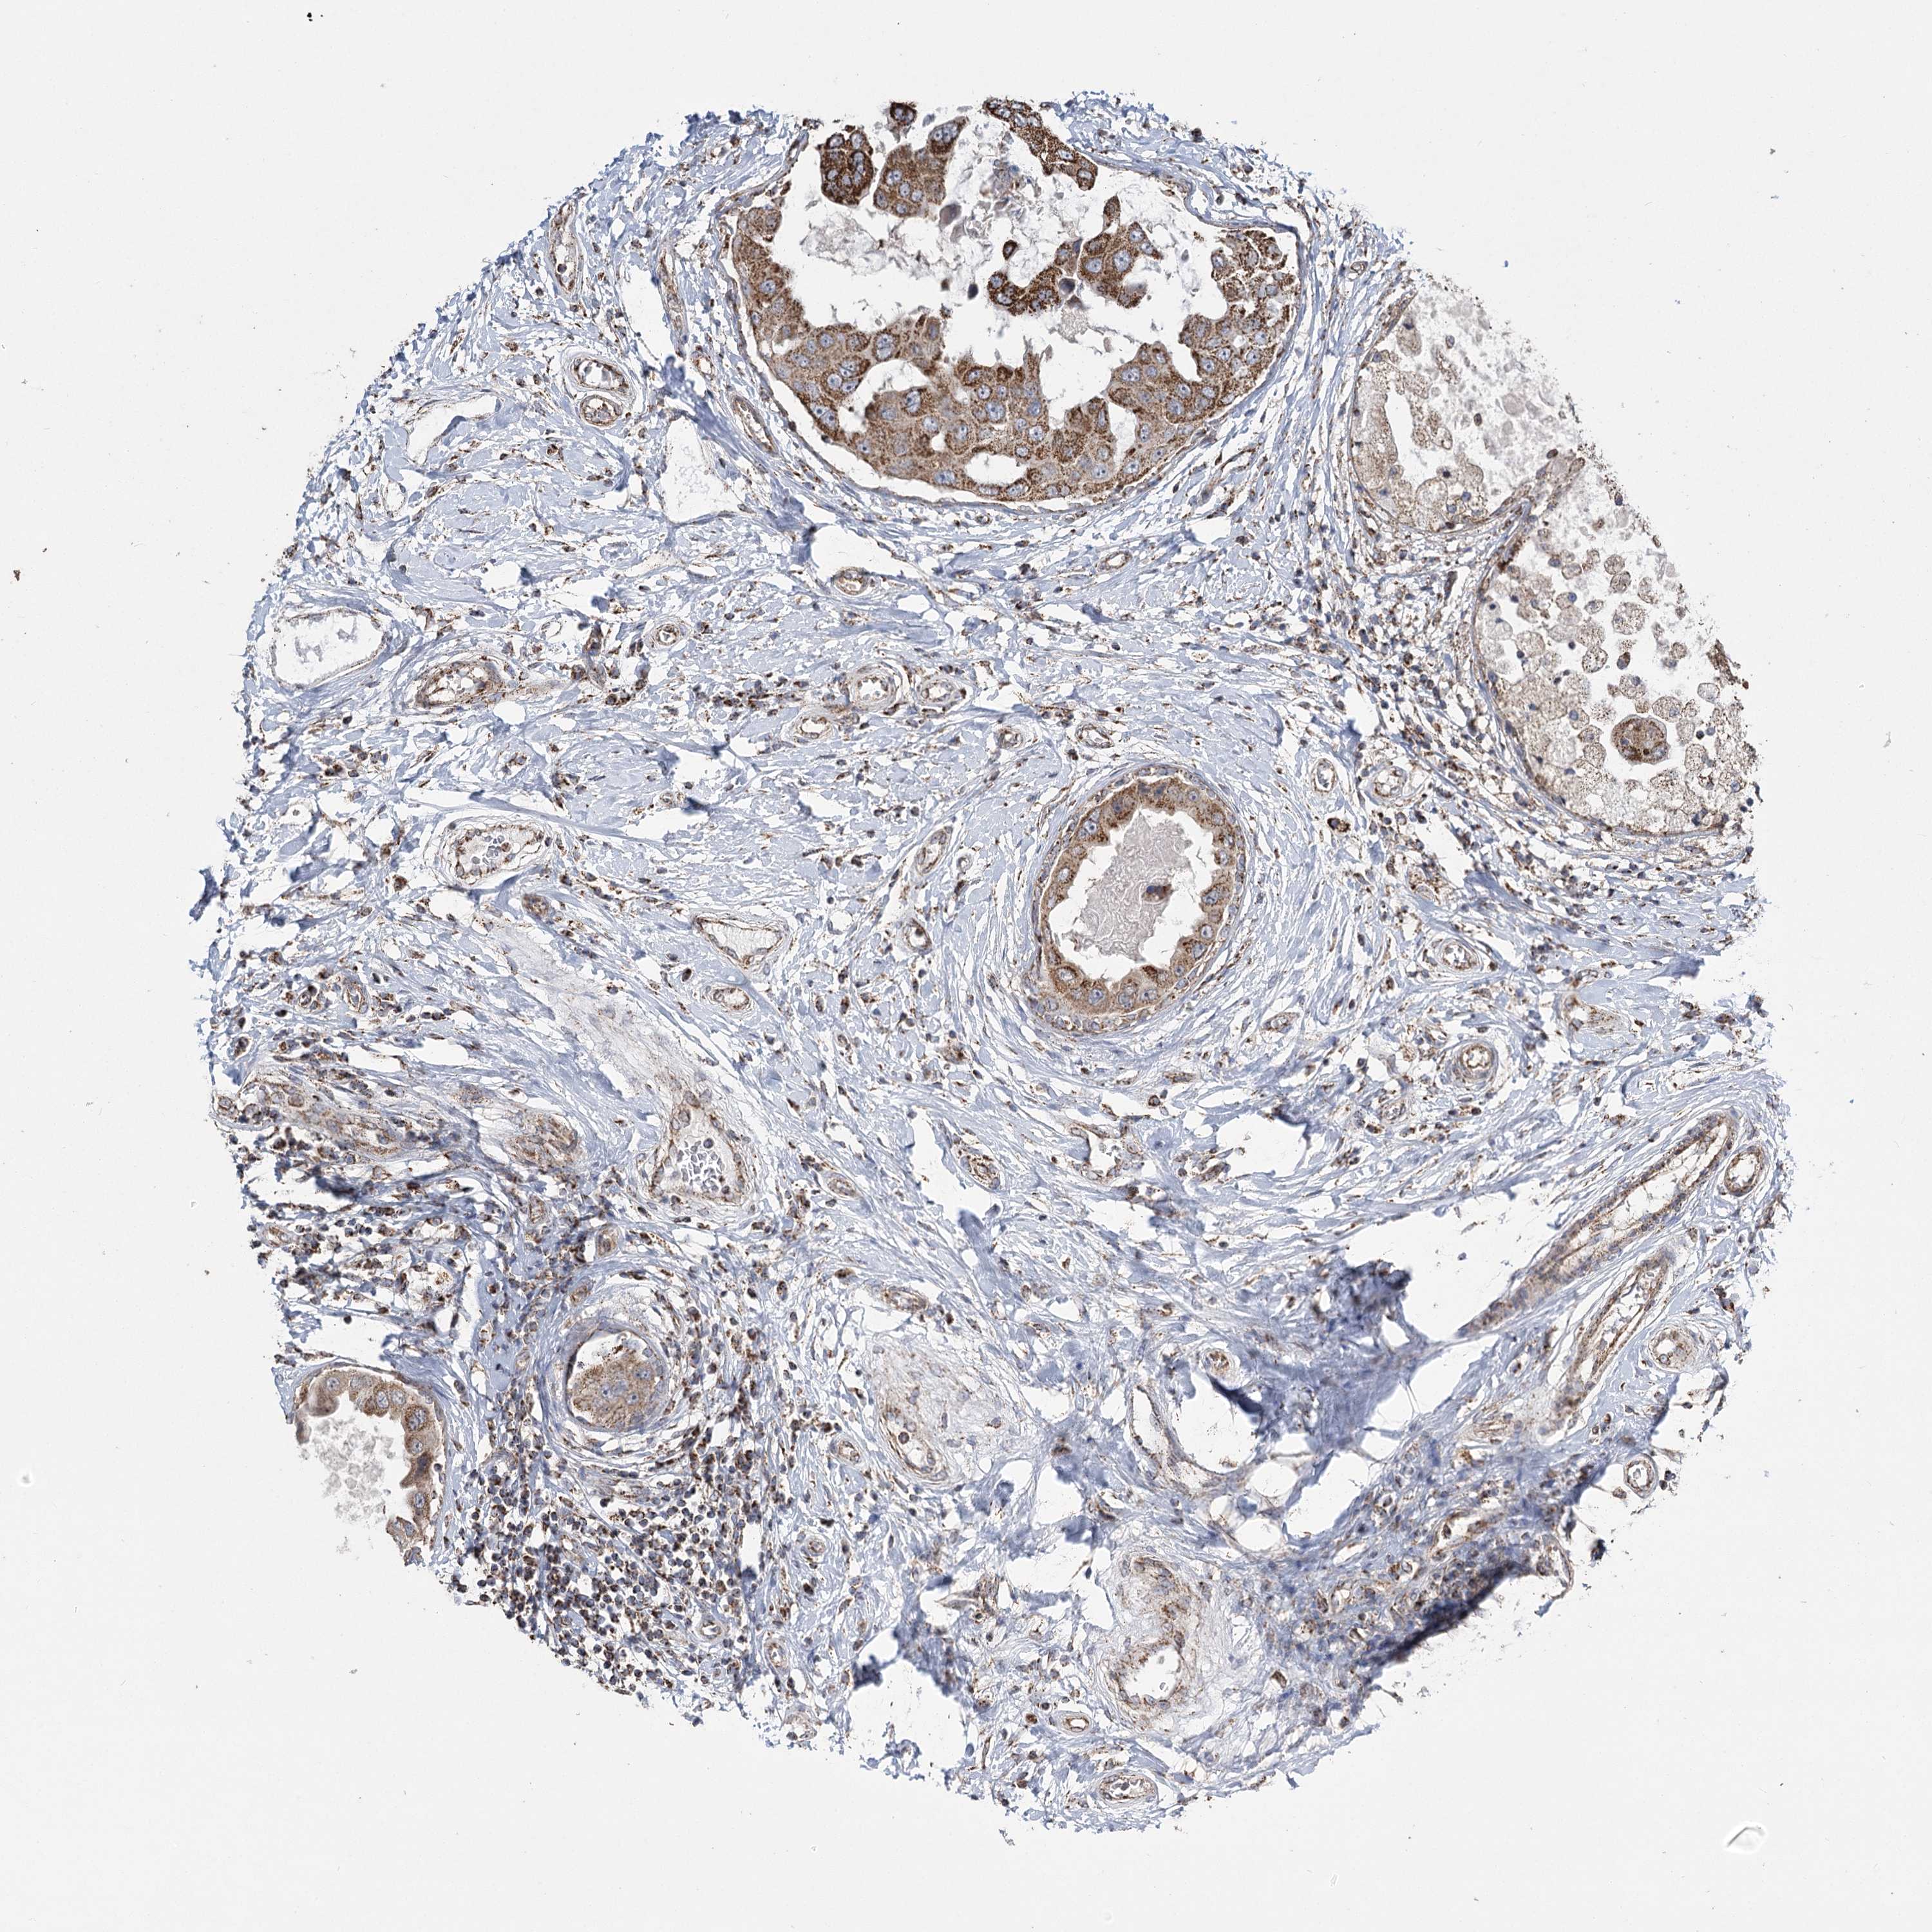

CANCER BREAST CANCER Show tissue menu

BRCA TCGA BRCA VALIDATION PROTEIN EXPRESSION